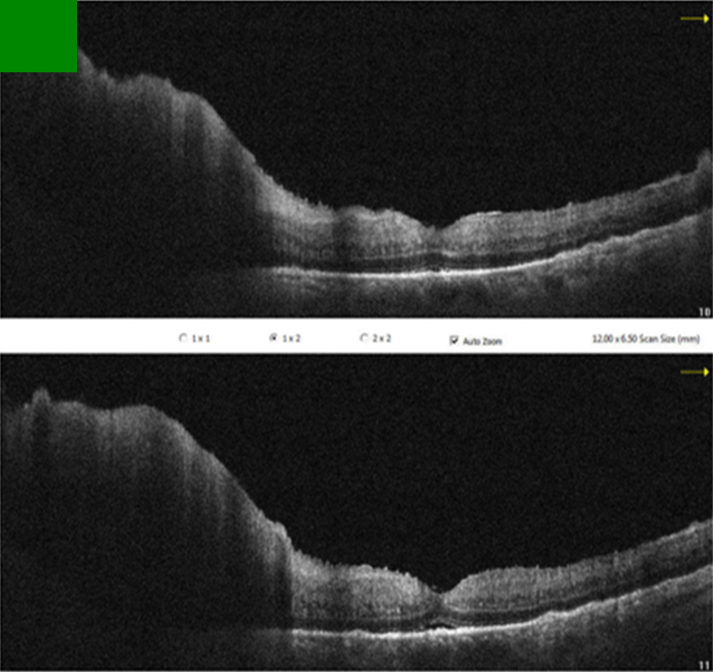

Since the visual acuity decreased to hand motion during systemic investigations, systemic steroid treatment was initiated with isoniazid (INH) prophylaxis. Following treatment, the vitreous inflammation in the left eye improved from +4 to +2 cells, allowing improved visualization of the posterior segment. The optic nerve appeared hyperemic and infiltrated, and the retina demonstrated diffuse white infiltrates with associated generalized retinal thickening, vascular sheathing, and venous beading, predominantly in the left eye (Figure 2 [Fig. 2]). Optical coherence tomography (OCT) showed irregularities and multiple subretinal hyperreflective deposits in the retinal pigment epithelium and Bruch membrane level, which were predominantly present in the left eye and severe optic disc edema (Figure 3 [Fig. 3]). Fundus fluorescein angiography (FFA) revealed indistinct granular changes and mild disc staining in the right eye. Active lesions were characterized by a typical early hypofluorescent pattern observed in the retinal infiltrates, with late hyperfluorescence containing dilated retinal vessels, diffuse pinpoint leakage at the infiltrative border in the left eye and areas of capillary dropout were observed (Figure 4 [Fig. 4]).

Figure 3: Pre-treatment OCT sections of the left eye

OCT revealed irregularities and multiple subretinal hyperreflective deposits at the level of the retinal pigment epithelium and Bruch’s membrane. These irregularities and deposits were predominantly observed in the left eye, accompanied by severe optic disc edema.

Metastasis of systemic lymphoma to the optic nerve is rare, with only one reported case out of nearly 6,000 cases [7]. Vitreoretinal involvement from non-central nervous system metastasis is also reported in only 5% of cases [2], [3]. While vitreous aspirates can detect lymphomatous cells in up to 40% of ocular lymphoma cases, vitreous biopsy remains the gold standard for diagnosis [8]. Typically, retinal involvement in lymphoma manifests as numerous subretinal orange-yellowish infiltrates which have the capacity to expand and conjoin over time, ultimately generating a sizable subretinal mass. Histopathologic evaluations have demonstrated these infiltrates to be deposits of lymphoproliferative cells located between the retinal pigment epithelium (RPE) and Bruch membrane [8]. Accordingly, there were diffuse white infiltrates in the retina and OCT showed irregularities and multiple subretinal hyperreflective deposits in the retinal pigment epithelium and Bruch membrane level, which were mostly seen in the left eye. We did not find any evidence of malignancy in the cerebrospinal fluid sample or vitreous aspirate.